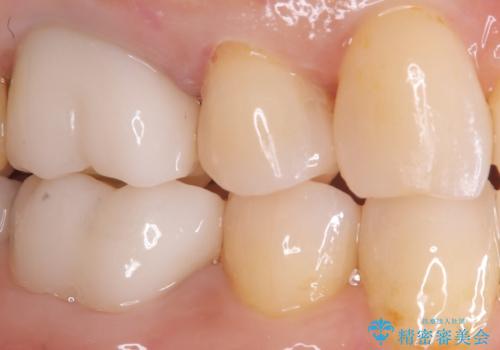

見た目も良く、満足していただきました。

セラミックインレーは、金属やプラスチックに比べ汚れが着きづらく、むし歯の再発リスクを減らすことができます。